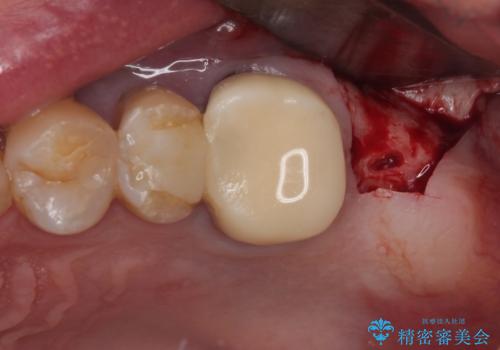

しかしながら、レントゲンやCT画像から、手前の破損したクラウンの根尖部に大きな病変が認められ、インプラント埋入部にまで病変が及んでいることから、まずは手前の根管治療を行い、病変の正体を確認した後にインプラント埋入を行うこととしました。

口があまり開かず、インプラントの埋入角度がやや斜めとなりましたが、機能的には全く問題なく治療を終えることができました。